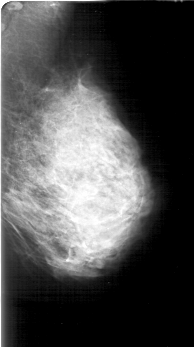

D_4192_1.LEFT_MLO

LEFT_MLO LINES 5896 PIXELS_PER_LINE 3286 BITS_PER_PIXEL 12 RESOLUTION 43.5 NON_OVERLAY